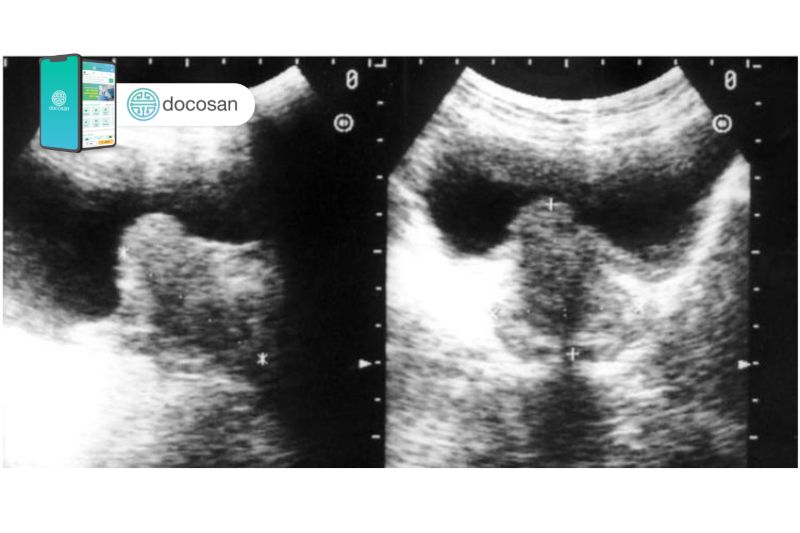

Tuy nhiên để có cái nhìn toàn diện hơn thì việc đánh giá thể tích tuyến tiền liệt có vai trò rất quan trọng trong chẩn đoán và theo dõi điều trị, trong đó siêu âm là phương pháp đánh giá được áp dụng rất rộng rãi với ưu điểm không gây sang chấn, thực hiện nhanh, chính xác, hiệu quả cao, giúp đánh giá thể tích tuyến tiền liệt và theo dõi u xơ tuyến tiền liệt.

Những phương pháp siêu âm tuyến tiền liệt gồm có siêu âm phía trên xương mu, siêu âm qua đường trực tràng, siêu âm qua đường tầng sinh môn, siêu âm bằng cách đưa đầu dò qua niệu đạo và siêu âm màu Doppler.